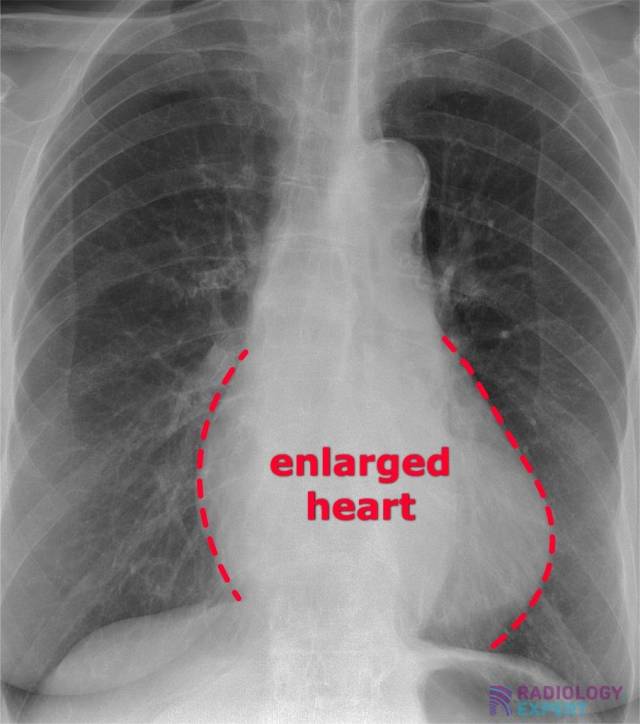

From www.radiology.expert

Chest Xray Would A Chest Xray Show An Enlarged Heart — an enlarged heart (cardiomegaly) isn't a disease, but rather a sign of another condition. Its presence may indicate fats and other substances in your. — an enlarged heart (cardiomegaly) describes a heart that’s bigger than what is typical. The term cardiomegaly refers to an enlarged heart seen on. You may not have symptoms. — mild cardiomegaly. Would A Chest Xray Show An Enlarged Heart.